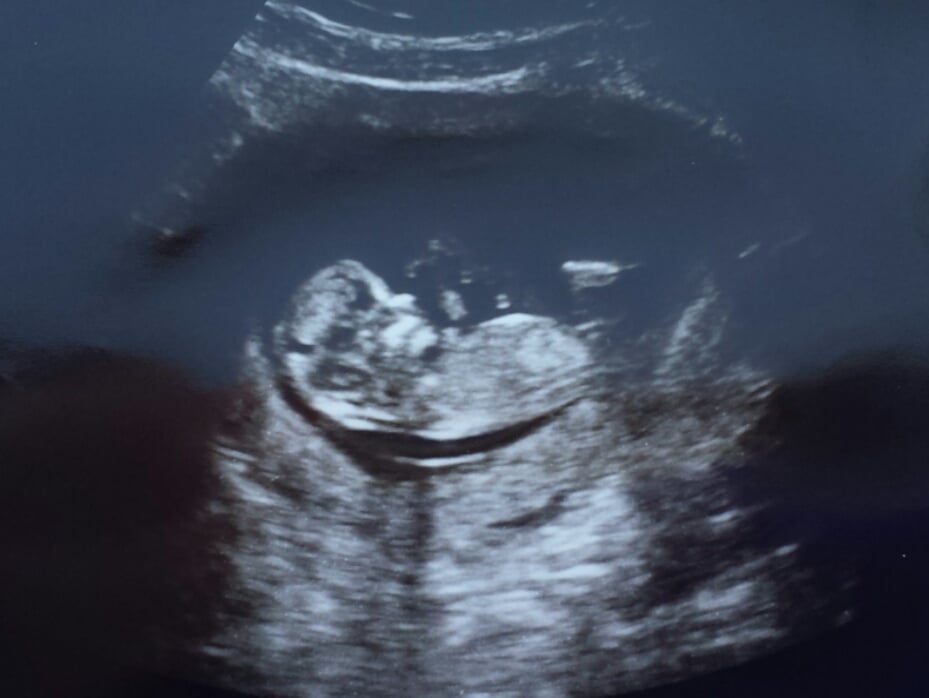

Finally have an us to share! LO is doing great at 12w3d NT scan (although they were very uncooperative in terms of getting into position!) Got to hear the heartbeat for the first time too. Feeling very relieved, especially after some spotting a few weeks ago. Love this pic because I think it looks like the baby's laughing.